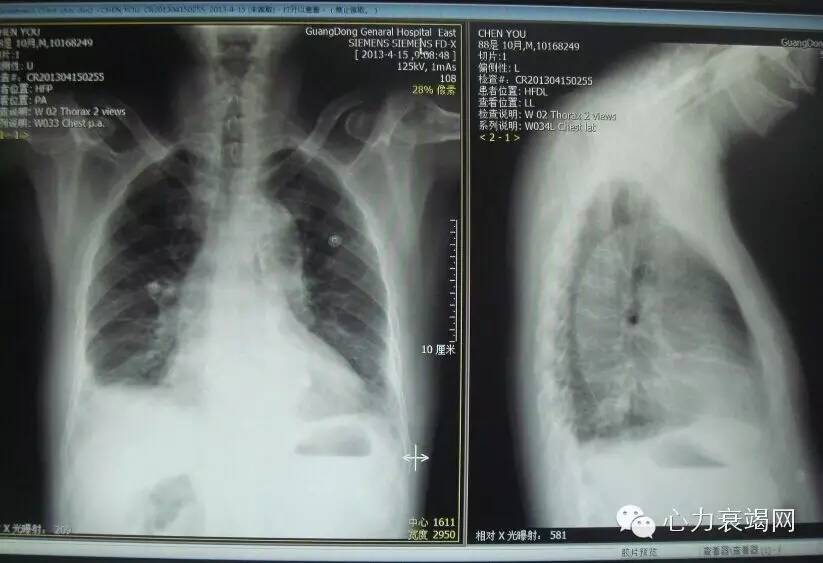

主诉:反复胸闷痛7年,胸闷、气促10天,于2013-04-01入院

现病史:7年前出现心前区胸闷痛,2006年出现急性下壁心肌梗死,CAG:LAD远端狭窄70-90%,LCX中段90%,RCA近端70-90%,中段闭塞,予PTCA,2013年胸闷、气促,CTnT811ng/L,Pro-NTBNP>9000pg/ml

T36.8℃, P88次/分, R 25次/分, BP 130/60 mmHg,贫血貌,颈静脉无怒张,双肺闻及细湿啰音,心界稍向左扩大,心音低钝,主动脉瓣及二尖瓣听诊区可闻及SM2/6吹风样杂音,双下肢水肿

冠心病,三支血管病变,陈旧性下壁心肌梗死,PTCA术后,急性非ST段抬高性心肌梗死,心力衰竭,心功能3级,高血压病,2型糖尿病,慢性支气管炎,G6PD贫血